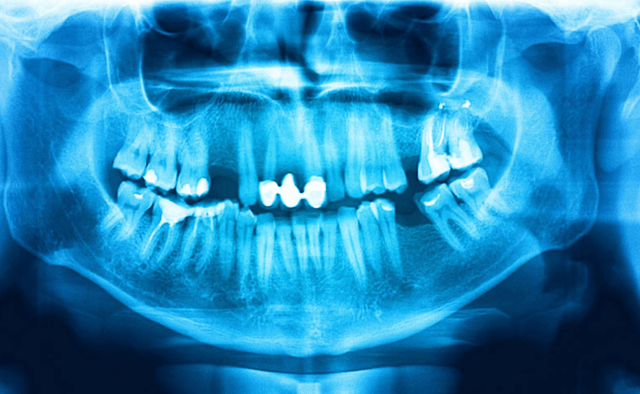

A study published by the Journal of the Irish Dental Association has found that Ireland is gripped by a tooth decay problem due to the mass fluoridation of their water supply.